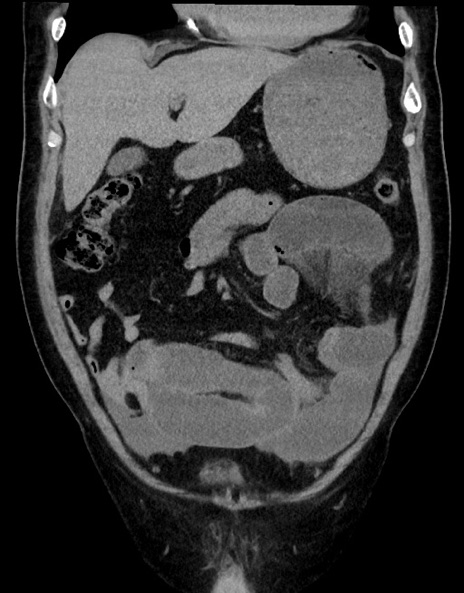

症例15(冠状断像)

【症例】70歳代男性

【主訴】腹痛

【現病歴】今朝から腹痛あり。全体的に痛い。特に左上の方。排ガスが今日はない。冷や汗が出る。

【既往歴】直腸癌術後

【身体所見】左側腹部〜上腹部に圧痛あり。腹膜刺激症状明らかなではない。軽度反跳痛。左下腹部に術後瘢痕あり。

【データ】WBC 7700、CRP 0.02